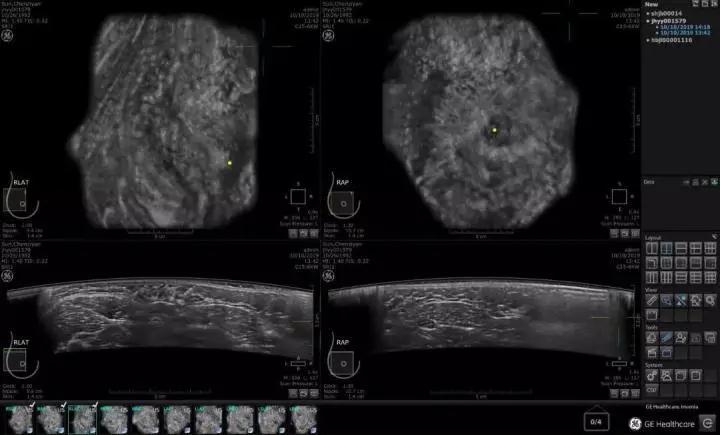

2012年9月26日,美国 FDA (食品药品监督管理局)批准了第一台用于乳腺癌筛查的超声设备。根据临床试验,应用ABUS超声系统进行读片比单独阅读乳腺钼靶摄片显著增加了乳腺癌的检出率,更适用于那些乳腺组织致密、钼靶摄片阴性且无乳腺癌症状的女性。到2019年10月,美国GE医疗推出全新一代的ABUS乳腺癌筛查系统,成为一款真正意义上适合中国乳腺癌标准化大规模的设备,它的优势在于:

中国70%女性为致密性乳腺,ABUS系统利用全新乳腺超声技术,能够清晰的观察致密性乳腺组织,适合在我国大量无症状人群中找到【0.1—2.0cm】的乳腺病变组织,也可用于有症状女性的超声诊断。

02 更精准的图像

15CM宽视野弧形探头,每秒300万像素的图像采集,毫无遗漏对全乳腺超声断层扫描(类CT),3D全容积成像,不依赖操作者的手法,全自动数据采集。图像数据存储云端,医生可多次读片,作前后图像数据对比。能帮助大量无病灶人群找到0.2cm以上微小病变组织。